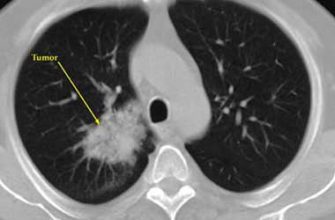

Дерматоскопия — это неинвазивкий метод осмотра кожных образований с использованием специального прибора, дерматоскопа. Этот прибор позволяет максимально подробно рассмотреть структуру и цветовые особенности кожных структур, что значительно повышает точность диагностики различных заболеваний, особенно меланомы и других злокачественных новообразований.

- Высокая точность и надежность диагностики, современные алгоритмы способны обнаруживать меланомы и другие кожные заболевания с точностью, не уступающей опытным специалистам.

Для работы систем ИИ применяются различные модели машинного обучения и глубокого обучения. Наиболее популярными являются сверточные нейронные сети (Convolutional Neural Networks, CNN), которые отлично справляются с анализом изображений.

Обучение таких систем происходит на больших наборах аннотированных данных, где каждое изображение помечено как доброкачественное или злокачественное, а также содержит описание характеристик. После обучения модель способна самостоятельно распознавать признаки и делать оценки.

Многие клиники и лаборатории уже успешно применяют системы ИИ для дерматоскопии. Например, крупные медицинские центры внедрили автоматические скрининговые системы, которые позволяют значительно ускорить поток пациентов и повысить точность диагностики. В некоторых случаях, системы показывают точность совпадений с диагнозом опытного дерматолога более чем 90%, что считается отличным результатом.